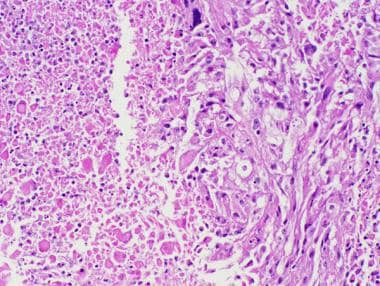

多形性黃色星形細(xì)胞瘤

單核炎性細(xì)胞浸潤(rùn)對(duì)于多形性黃色星形細(xì)胞瘤并不少見。(蘇木精和曙紅,40×原始放大倍數(shù)。)

多形性黃色星形細(xì)胞瘤可能在診斷時(shí)或多年隨訪后顯示壞死區(qū)域,這一特征被國際衛(wèi)生組織(世衛(wèi)組織)認(rèn)為符合“具有間變性特征的多形性黃色星形細(xì)胞瘤”的診斷標(biāo)準(zhǔn)(蘇木精和曙紅,20倍原始放大倍數(shù)。)